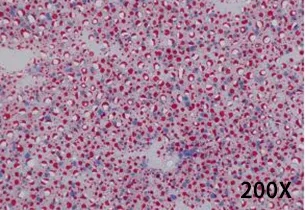

04 组织病理学

对照组肝细胞呈多边形,细胞质丰富,细胞核位于细胞中央,小叶结构清晰,肝细胞无脂肪变性,汇管区未见炎细胞浸润,无其他病理改变。模型组小鼠肝细胞明显肿胀,细胞质内明显可见脂肪空泡,脂滴融合导致细胞核偏位,甚至细胞核消失,肝组织内可见弥漫分布的大油滴和微小脂滴,并散布全肝,肝细胞有明显的炎症变化 。

图5. C57BL/6N-对照组-油红O染色。

图6. C57BL/6N-高脂诱导4周-油红O染色。

图7. C57BL/6N-高脂诱导12周-油红O染色。